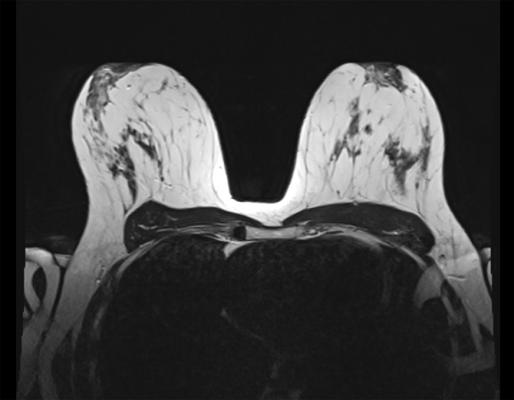

Bayer initiated the QUANTI studies to evaluate the safety and efficacy of gadoquatrane, an investigational gadolinium-based contrast agent, in MRI. Contrast-enhanced MRI plays a key role in the healthcare continuum, providing a radiation-free imaging method to obtain detailed images of the body.

- QUANTI OBR investigates the safety and efficacy of gadoquatrane in contrast-enhanced MRI of all other body regions, such as head and neck, thorax, abdomen, pelvis, and extremities.